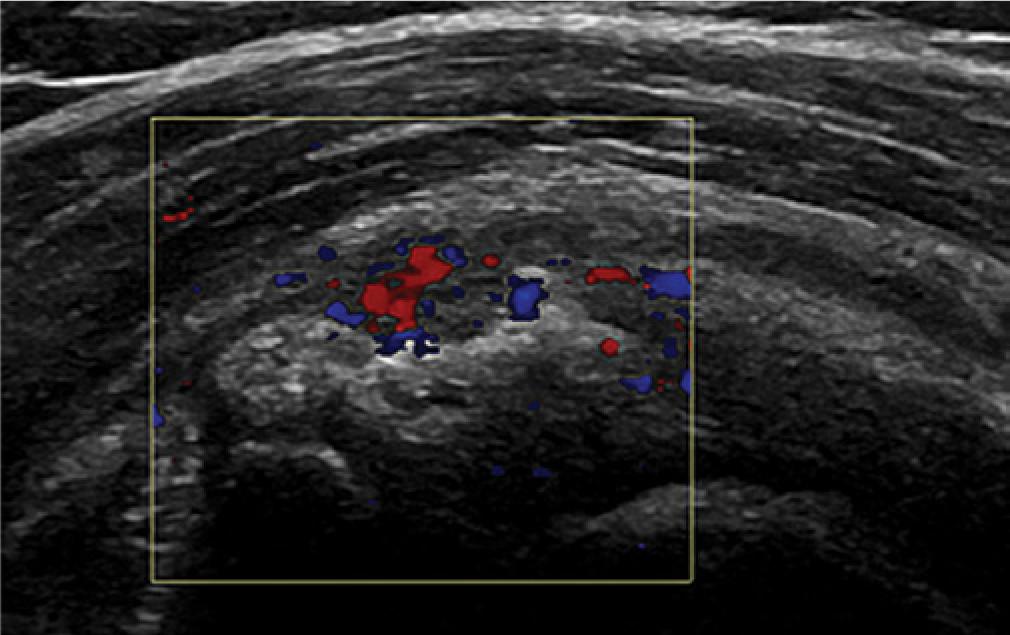

Acute calcification causing tendinosis will have neovascularization around it and in the adjacent tendon. (Fig. 6). Hard, established calcification will not have neovascularization around if it is quiescent and not causing tendinosis. The calcified area may give a mass effect which will impinge as the shoulder is moved, however. It is also important to assess calcification within a tendon dynamically. This hard calcification normally gives acoustic shadowing behind it.

Calcific tendinosis with loss of the subdeltoid subacromial bursal interface, acoustic shadowing and neovascularization